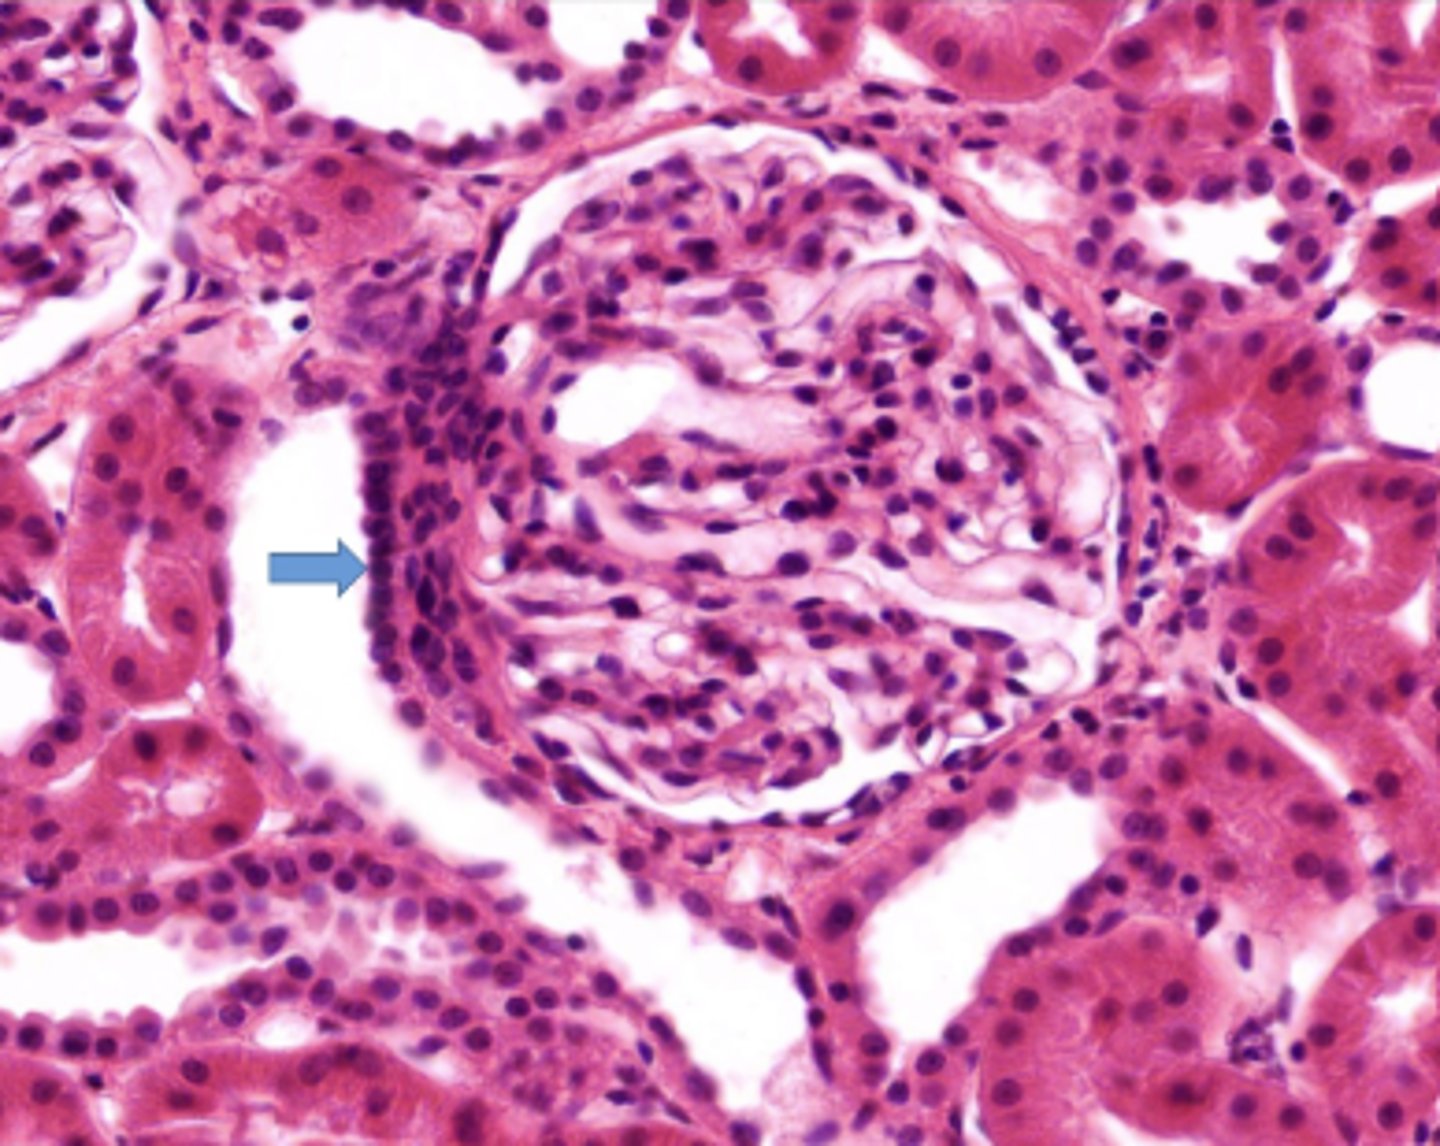

glomerulus

Identify this portion of the glomerulus, communicating with the efferent and afferent arterioles

vascular pole

Identify the nuclei on the distal convoluted tubule

macula densa

Identify the structure of the glomerulus at 2

urinary pole

The arrow shows where filtrate enters what segment of the nephron

proximal convoluted tubule

What joins the glomerulus at the vascular pole of the renal corpuscle

afferent and efferent arterioles